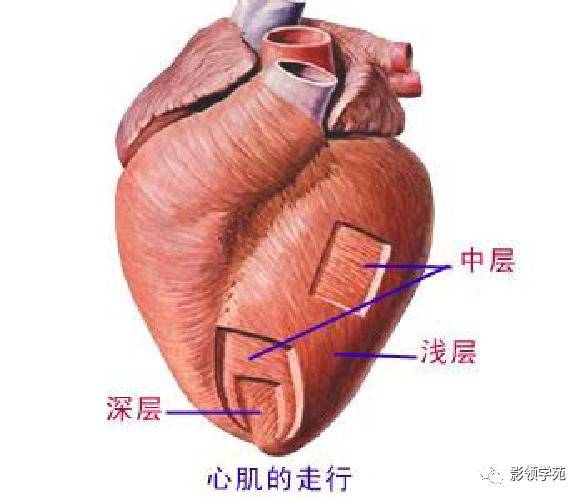

心血管系统

心血管系统